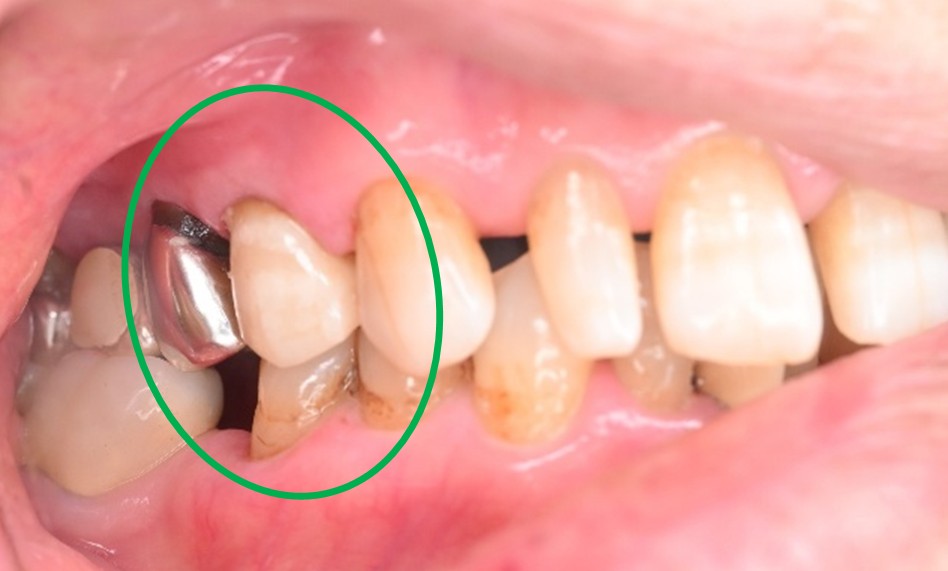

右下のブリッジがゆらゆら動く。

治療内容

ブリッジの支台になっている奥の歯が、被せ物の中で虫歯になり、支台の役割を果たさず、前方の歯のみで支えられていました。前方の歯をそのままにして、後方の部分を切り離すと、そのまま取れてきました。中は、虫歯で歯根しか残っていない状況でした。この歯は、根管治療後、単独でオールセラミック冠を被せ、歯のないところにインプラントを埋入しました。

所感

今回の治療法には、次の3つの方法があります。

(1)虫歯になっていた歯の根管治療をし、土台を入れ、また再びブリッジにする。しかし、虫歯になっていたほうの歯は、ブリッジの支台として使うには、心もとなく長持ちしない可能性が高く、今度問題が生じたときには抜歯になる。

(2)虫歯になっていた歯に、単独で被せ物をし、歯のないところに1本だけの部分入れ歯を入れる。取り外しの入れ歯なので、自分の歯のような感覚で噛むことはできない。この方法も歯のない部分の負担を欠損の両側の歯に負担してもらうため、長持ちしない可能性が高い。

(3)虫歯になっていた歯に、単独で被せ物をし、歯のないところにインプラントを埋入する。欠損している部分の負担を前後の歯に負担させないので、歯を守ることができる。また、自分の歯と同じ感覚で食事をすることができる。

患者さんは、3つ目の方法を選択されました。一番長持ちし、これ以上歯を失わないためには、最良の方法だと考えます。

オールセラミック冠(失活歯):¥104,500(税込)

インプラント:¥363,000(税込)

合計:¥467,500(税込)

Before

冠の中で大きな虫歯になり支台の役割を果たしていませんでした。

【インプラント埋入前】

冠はブリッジを切断しただけで取れてきました。軟化象牙質を取り除いたところ、歯根しか残っていない状況で保存できるかどうかのぎりぎりのところでした。